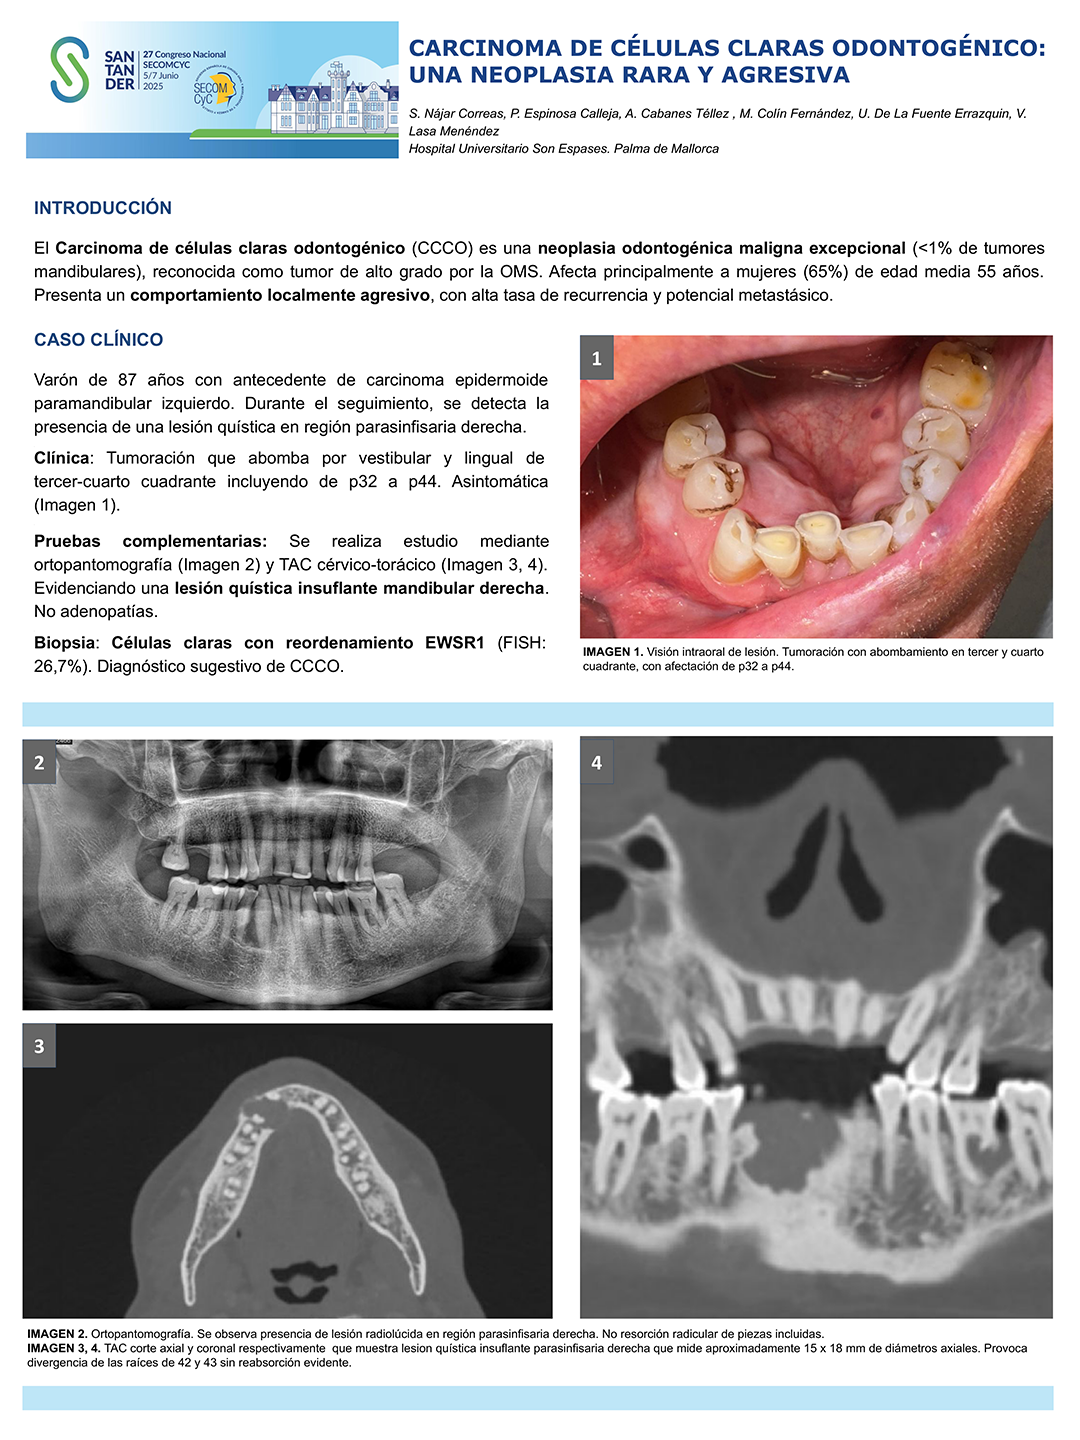

CARCINOMA DE CÉLULAS CLARAS ODONTOGÉNICO: UNA NEOPLASIA RARA Y AGRESIVA

SN

Sara Nájar Correas Autor

Patología de la articulación temporomandibular

Diapositivas: 2

162